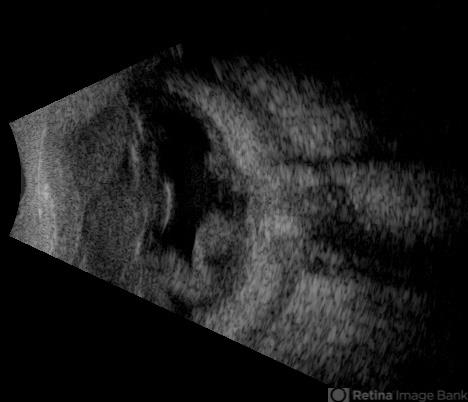

- T sign, blunt trauma, retinal detachment

- This B-mode axial ultrasound scan reveals vitreous hemorrhage, a folded retinal detachment, and sub-Tenon’s fluid extending into the optic nerve sheath, forming the characteristic 'T-sign.' These findings are consistent with severe posterior segment trauma secondary to blunt ocular injury.